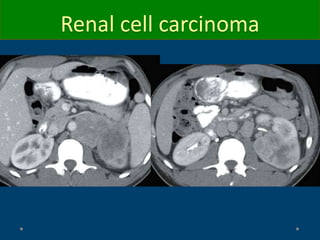

Renal cell carcinoma

CT

o Hypervascular mass and heterogeneous: clear cell

o Homogeneous (papillary<3cm)

o Poorly enhancing(10-20 HU) = papillary, chromophobe

o Calcification:

• Thin peripheral curvilinear: cyst

• Central or thick mural calcification: RCC

o Typically exophytic but may be intrarenal or infiltrative

o Necrosis

o Incidental finding